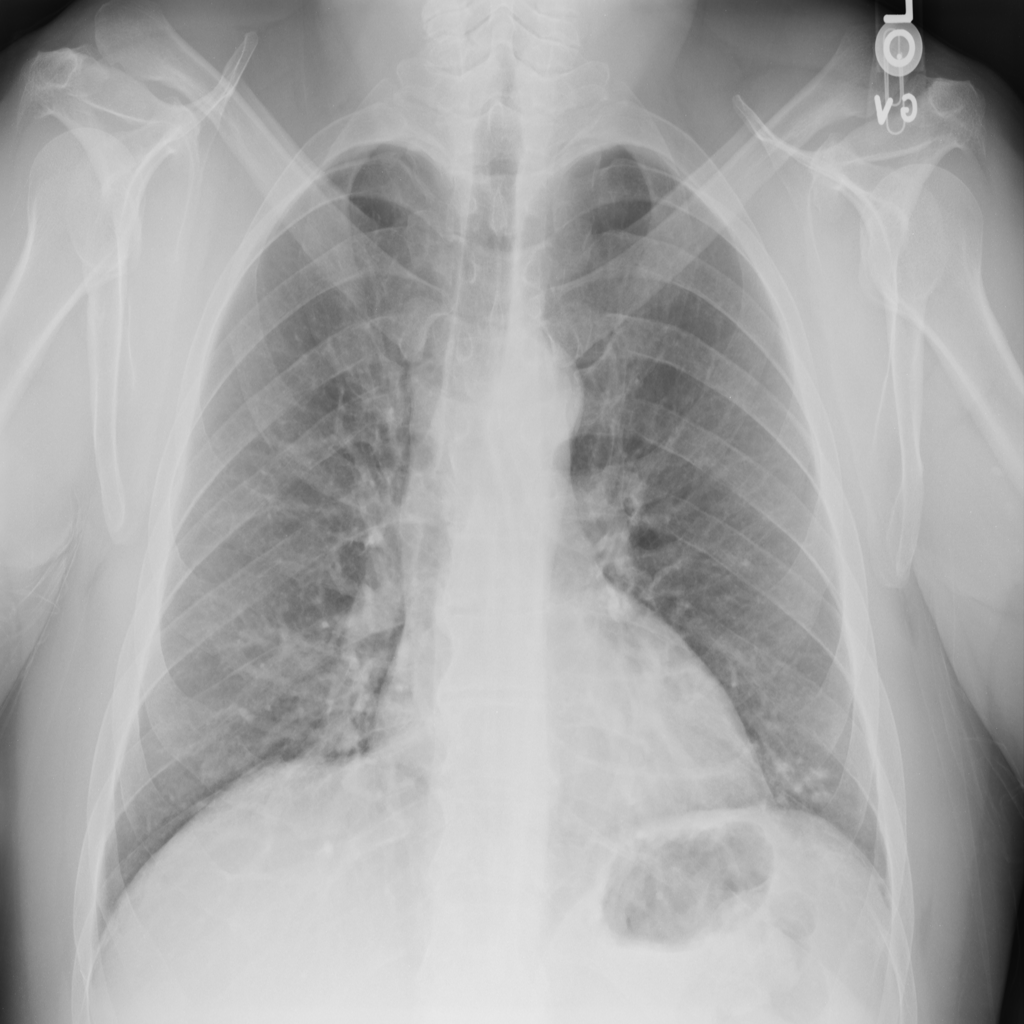

Nodule

A nodule is a small rounded opacity in the lung or chest field. It is a descriptive imaging finding that can be benign or more concerning depending on size, appearance, and context.

Showing up to 90 reference images for Nodule.